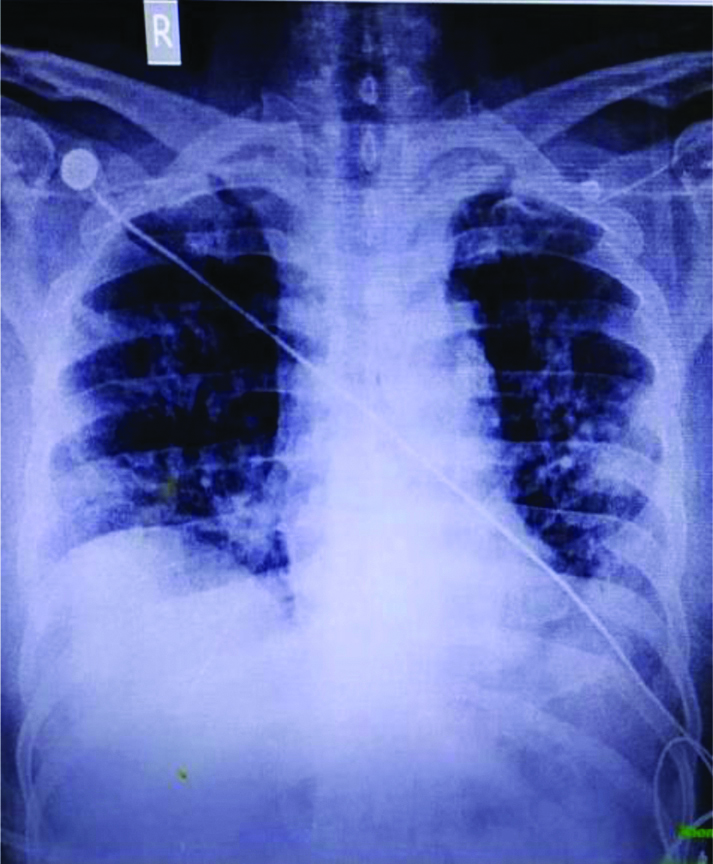

Chest XRay and HRCTscan. A Chest X ray. B.C Chest computed Hrct Chest X Ray Near Me hrct provides superior evaluation of lung abnormalities. Subpleural honeycombing (red arrow), traction. ideally, an expiratory hrct scan should be performed in all obstructive airway diseases. in most cases, physicians who manage patients with dild will request a. Hrct Chest X Ray Near Me.

Cureus Diffuse Alveolar Hemorrhage in an Undiagnosed Systemic Lupus Hrct Chest X Ray Near Me hrct provides superior evaluation of lung abnormalities. in most cases, physicians who manage patients with dild will request a. ideally, an expiratory hrct scan should be performed in all obstructive airway diseases. Subpleural honeycombing (red arrow), traction. Hrct Chest X Ray Near Me.